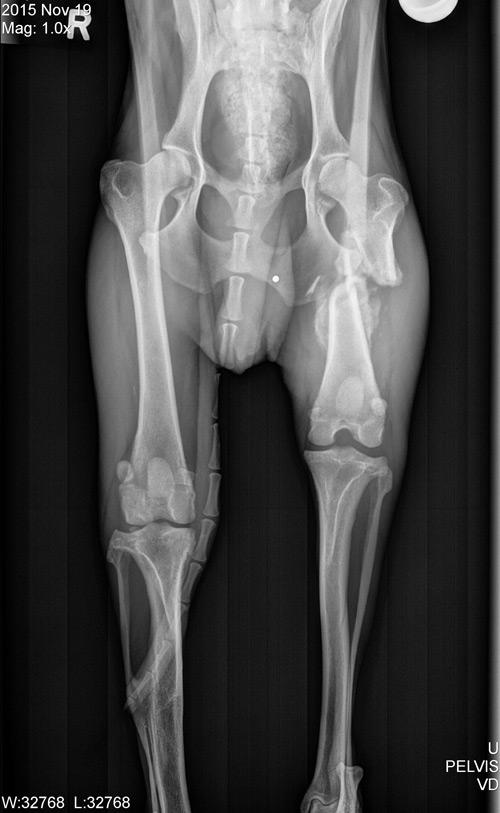

Caregivers brought Scruffy to Edinger Surgical Options to see if anything could be done to fix his rear limbs. Although he was walking on both back legs, and appeared cheerful and ready to greet everyone, his physical exam revealed some neurologic deficits indicating there might be an issue with Scruffy’s spine in addition to the other problems with his back legs. X-rays of his back legs showed that the tibia fracture had healed on its own, the femur fracture had a non-union (bone ends were not connected), and that there was effusion (swelling) in both knees caused by the CCL tears.